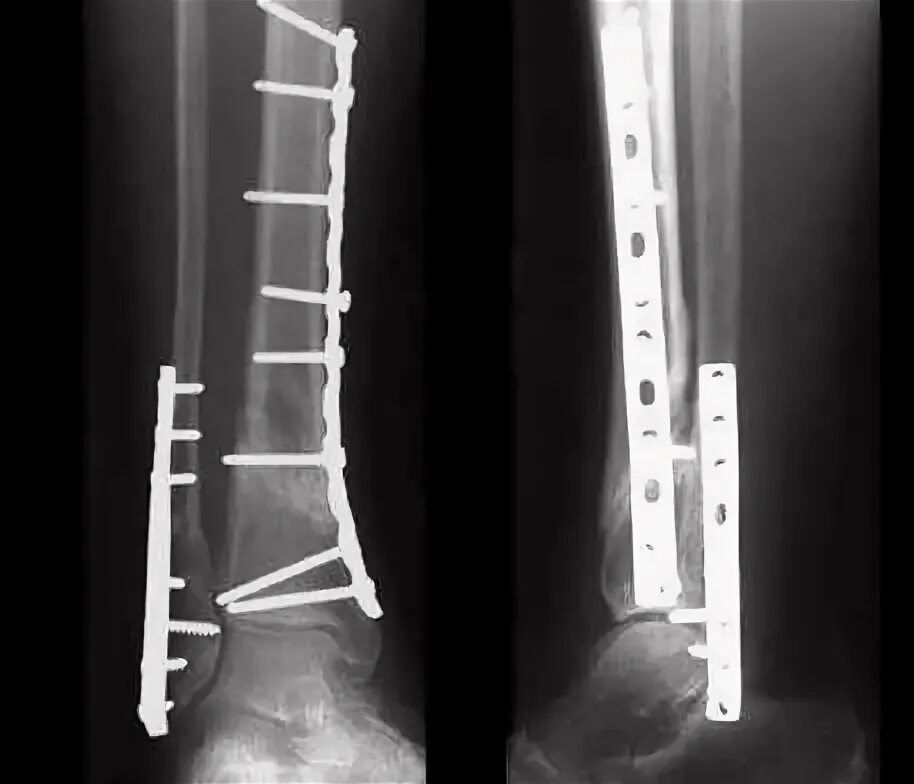

После остеосинтеза лодыжек